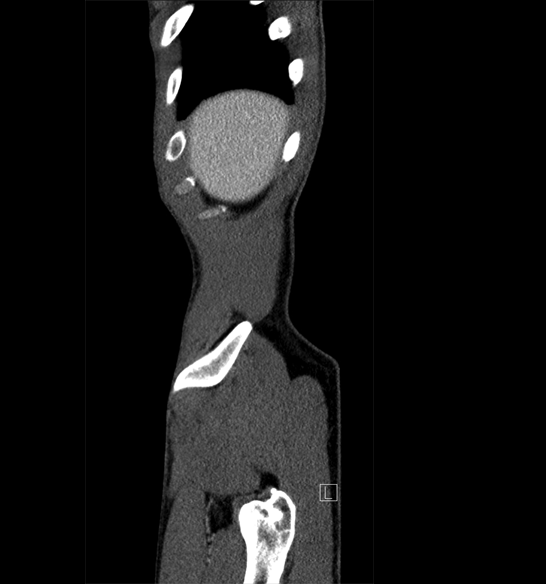

Body

Covers abdominal CT anatomy.